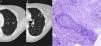

In a radiological follow-up of the disease, when the patient was asymptomatic, a chest X-ray and computed tomography (CT) were obtained, showing 2 solid cavitating nodules, one measuring 15mm in the apicoposterior segment of the left upper lobe (Fig. 1A) and the other 24mm in the upper segment of the lingula (Fig. 1B).

(A) Chest CT showing a cavitating nodular lesion in the left upper lobe and (B) another in the upper segment of the lingula. (C) Staining of elastic fibers to highlight the irregular destruction of the arterial wall by the inflammatory process. Necrosis is seen in the upper right corner. Orcein 200×.

A pulmonary biopsy was obtained from the lingular lesion using CT-guided Tru-Cut. Histopathological study showed a granulomatous inflammatory lesion associated with vasculitis consistent with granulomatosis with polyangiitis (formerly known as Wegener's granulomatosis) (Fig. 1C).